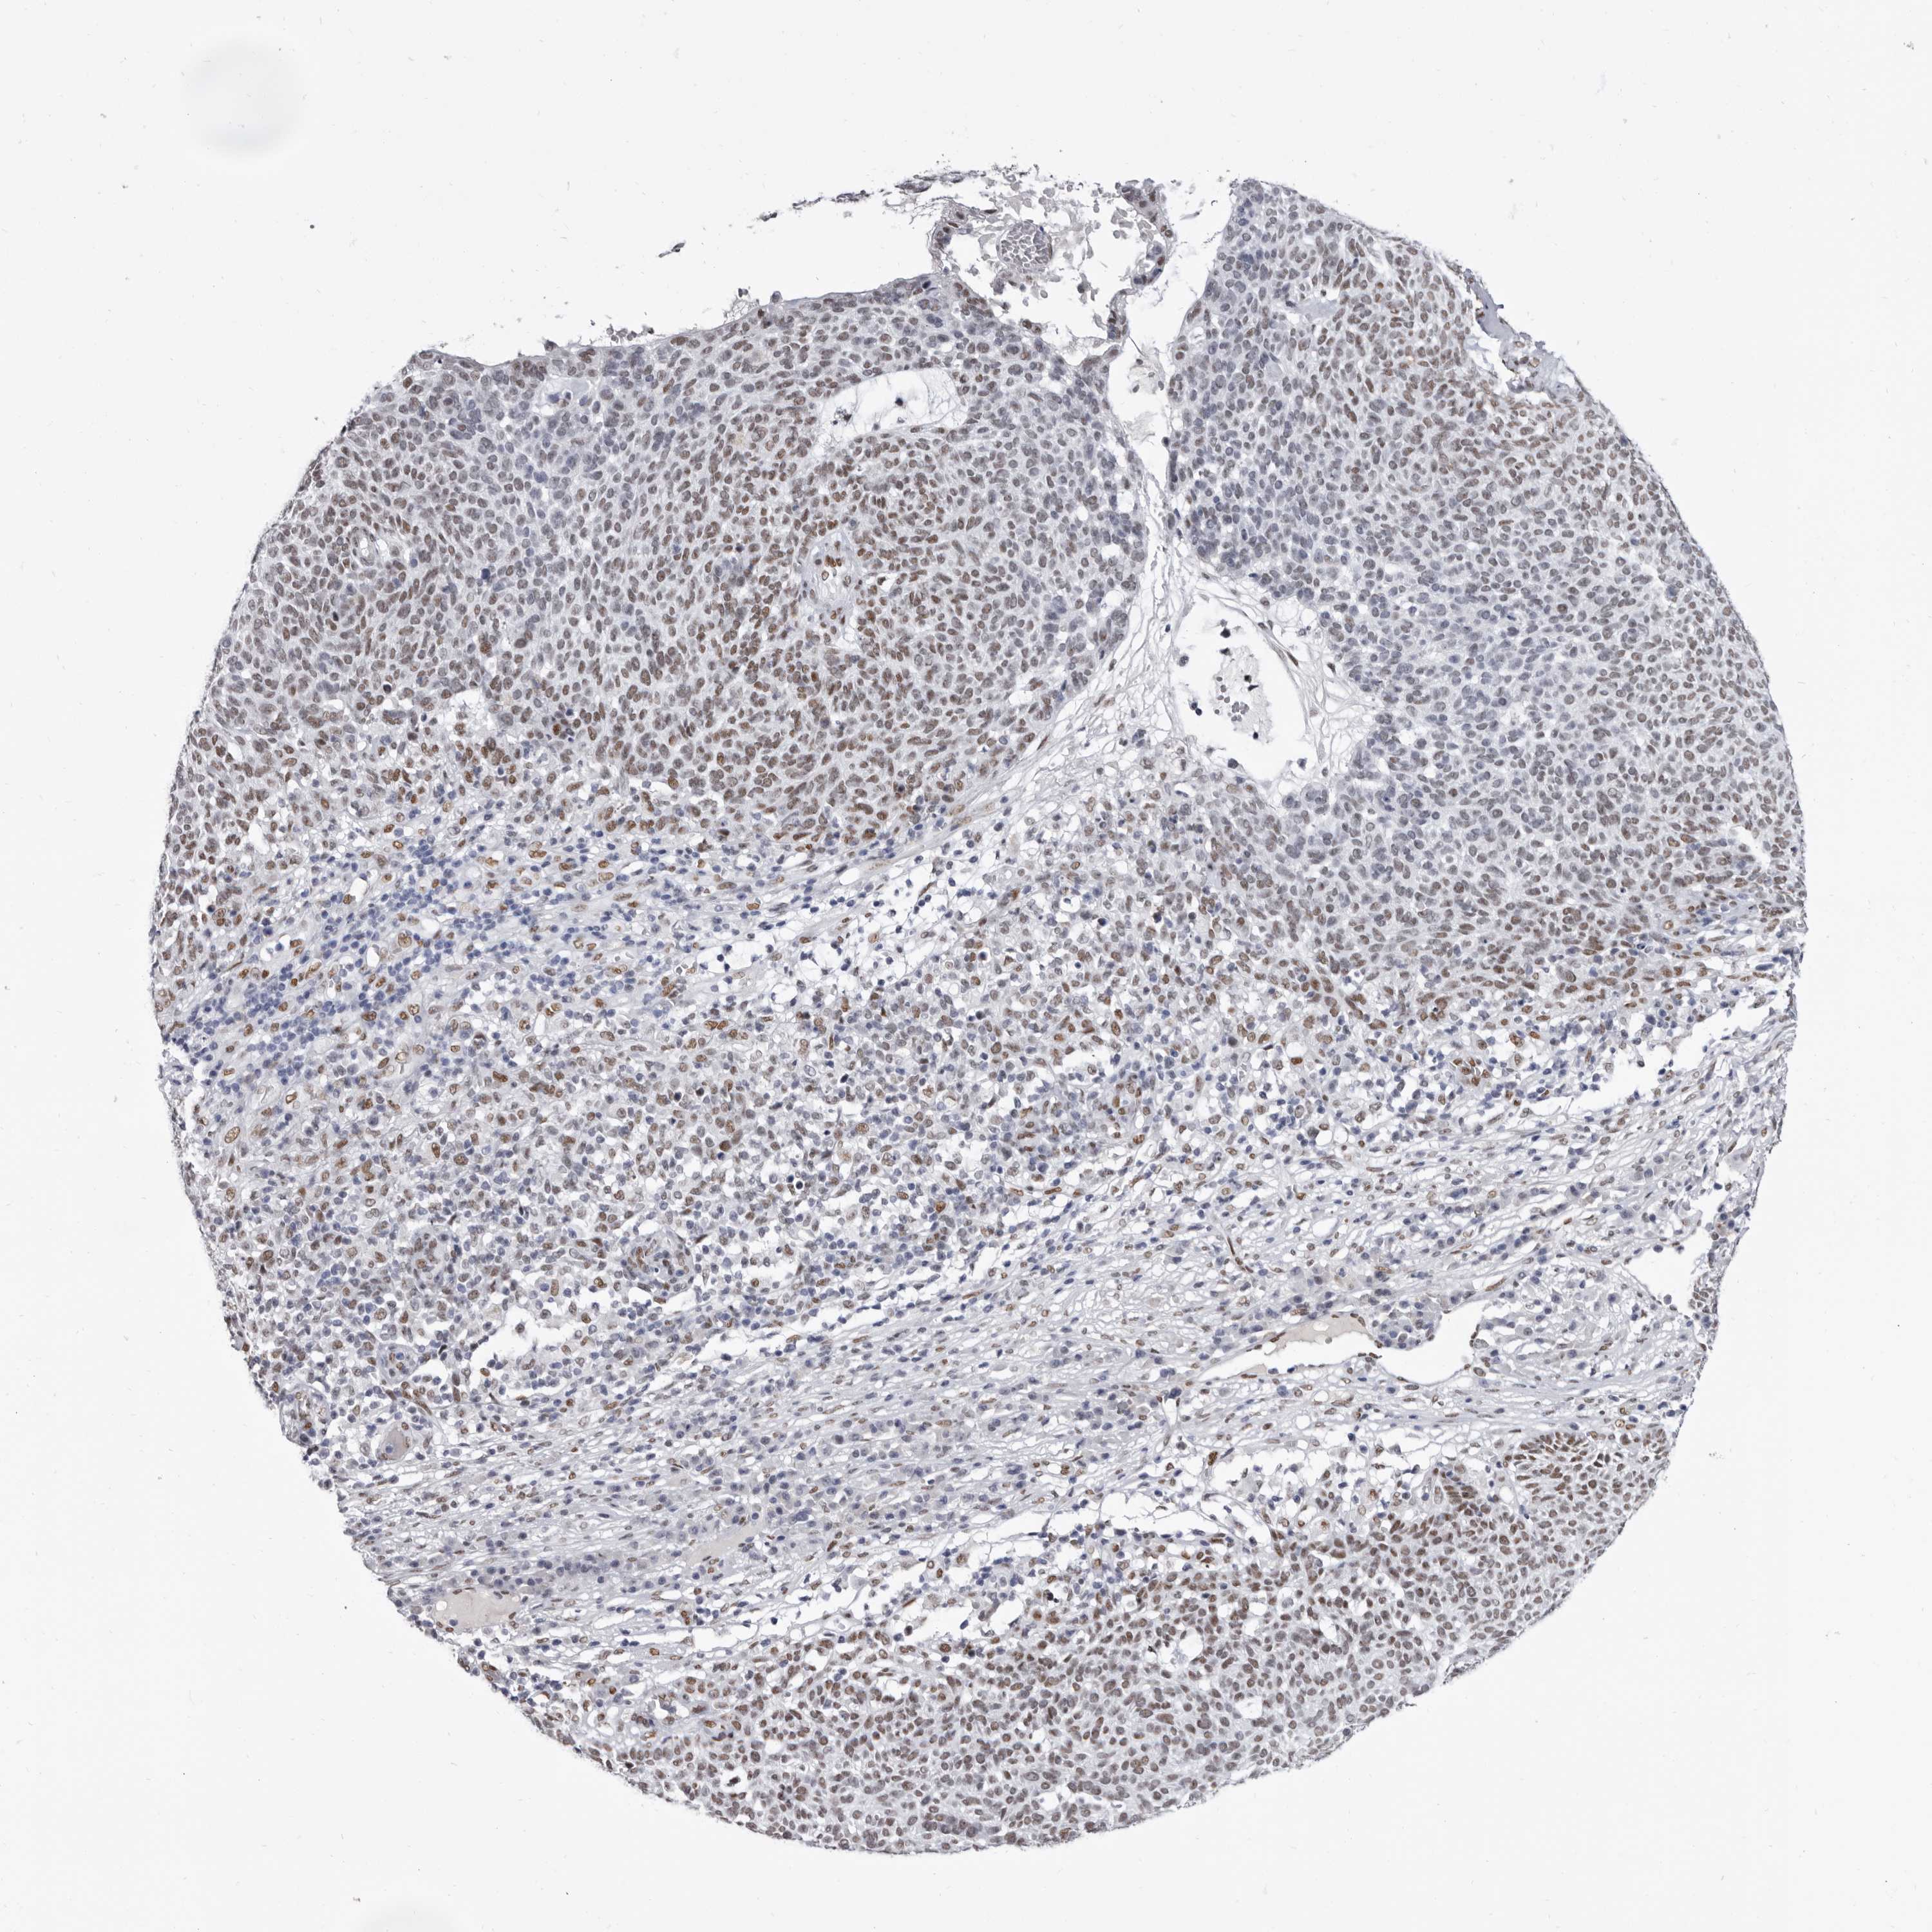

SKIN CANCER - Protein expressioni

A mouse-over function shows sample information and annotation data. Click on an image to view it in a full screen mode. Samples can be filtered based on level of antibody staining by selecting one or several of the following categories: high, medium, low and not detected. The assay and annotation is described here.

Antibody staining in the annotated cell types in the current human tissue is reported as not detected, low, medium, or high, based on conventional immunohistochemistry profiling in selected tissues. This score is based on the combination of the staining intensity and fraction of stained cells.

Each image is clickable and will lead to virtual microscopy that enables deeper exploration of all samples and also displays staining intensity scores, fraction scores and subcellular localization as well as patient and tissue information for each sample.

Antibody HPA028461

Antibody HPA028466

Basal cell carcinoma